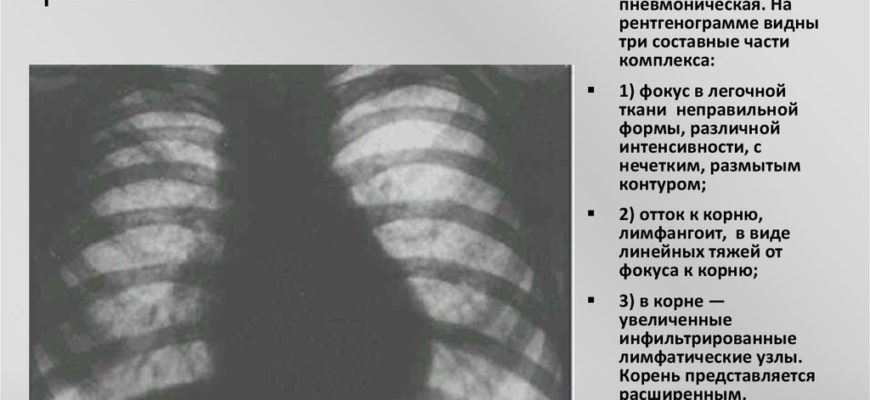

Помимо локализации и частоты патологического процесса, рентгенограммы легких также помогают определить стадию заболевания. Радиологическая классификация стадий развития ПТК:

- Пневматический. На изображении очаг поражения в легочной ткани определяется как затемненный очаг неправильной или овальной формы, часто сливающийся с корнями легкого. Из-за интенсивности тени пораженные увеличенные лимфатические узлы чаще всего незаметны.

- Организационный этап. На рентгенограмме очаг затемненияуменьшается в размерах, но лимфатические узлы становятся отчетливыми (симптом Редекера или «биполярность»), соединенные линейной тенью. Это соответствует течению пораженных лимфатических сосудов.

- Этап уплотнения и организации. В этой фазе начинается отложение солей кальция в очаге туберкулезной инфекции с последующим формированием очага Гона.